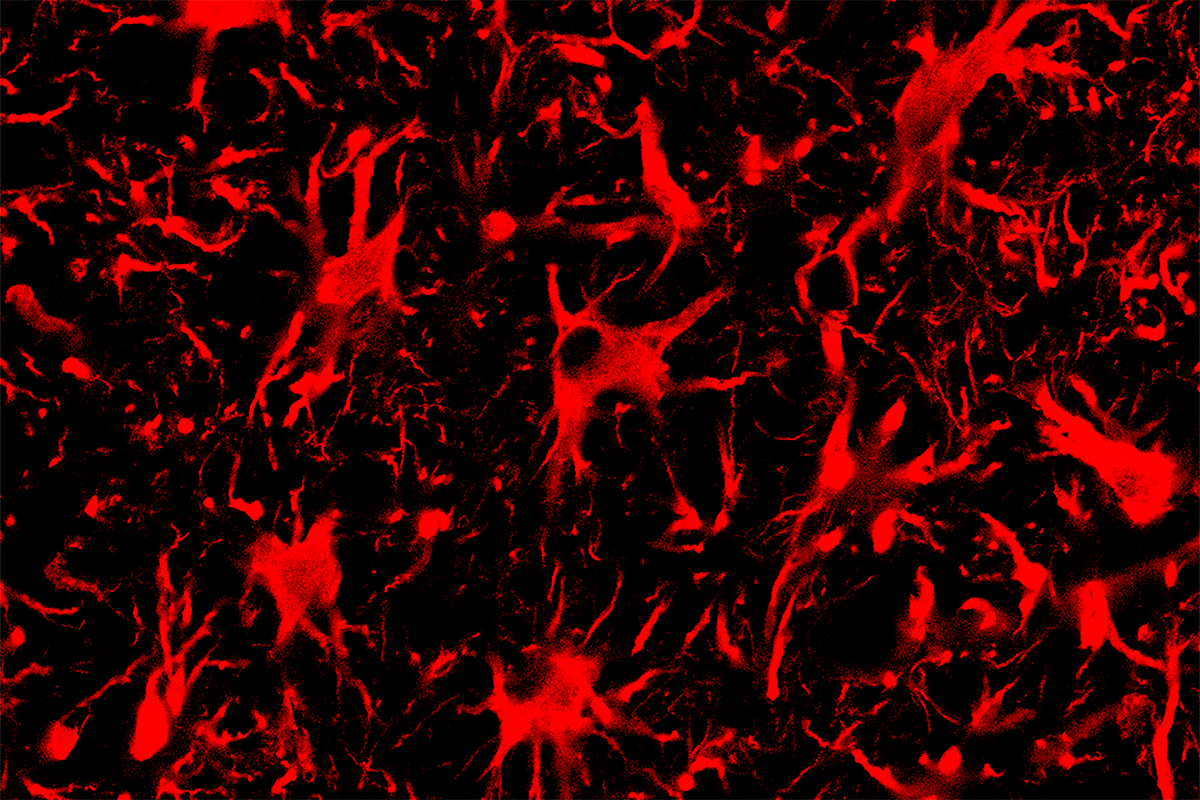

The researchers injected the CRISPR-Cas13 systems to the central nervous systems of mice with genetic mutations that cause ALS or Huntington’s disease. Adeno-associated virus vectors carried the RNA-targeting systems to cells. These vectors are a promising vehicle for gene therapy due in part to their ability to enter cells within the spinal cord and brain, Gaj said.

The researchers found that CRISPR-Cas13 effectively reduced the amount of mutant protein present in the nervous system for both diseases – specifically, the protein SOD1 within the spinal cords of mice with ALS, and the protein “huntingtin” within the brains of mice with Huntington’s disease. The reduction in mutant SOD1 protein also correlated with better therapeutic outcomes: Mice with ALS that received the CRISPR-Cas13 injection had slower disease progression, improved survival and a slower rate of decline in grip strength and motor skills compared with mice that did not receive the treatment.